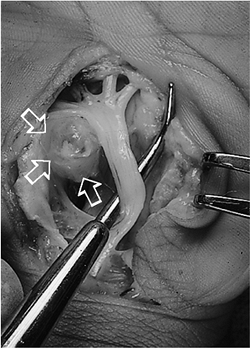

Figure 3-6

This large ganglion cyst arose from the volar aspect of the carpal

canal, and caused median nerve complaints. The ganglion is to the left (arrows) and the probe is deflecting the median nerve.

Figure 3-7 (A)

Ganglions may arise in the substance of extensor tendons, and present

as a mass that moves distally with flexion of the fingers. (B) The ganglion cyst is fusiform in shape. (C) It can be removed without loss of integrity of the extensor tendon. -